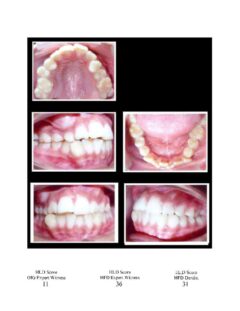

So here again are photos of children’s teeth that were pre-approved for treatment by the state’s Medicaid claims administrator TMHP/ACS, that HHSC-OIG now claims were fraudulently scored by Medicaid dental providers. These cases are from the SOAH hearings that have been completed for Harlingen Family Dentistry and Antoine Dental Center. The SOAH courts found both practices innocent of any allegation of Medicaid fraud or misrepresentation. The photo pages show the attending dentist’s HLD score, the dentist’s expert witness score and the OIG expert’s score.

Harlingen Family Dentistry